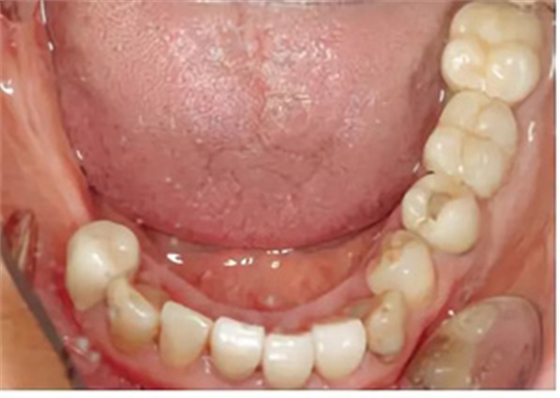

口外檢查未發(fā)現(xiàn)異常。牙齒和牙周狀態(tài)如圖1 和2-6所示??傮w來說,已有的修復(fù)體已不完善。第一次就診時(shí),檢查發(fā)現(xiàn)17、15、11、36、45 和46 號牙齒已缺失。16、14、12、27、37 和35 號牙齒已做過根管治療。所有剩余的牙齒牙髓活力測試均正常,叩診檢查未見異常。橋基牙37 已發(fā)生大面積的繼發(fā)齲,33 號牙齒齲壞和43 號牙齒繼發(fā)齲。16 和14 號牙齒根管充填不足且有根尖周炎。35 號牙齒的根管充填似乎是邊緣封閉、無氣泡,但也欠充。所有需要保留的牙齒的平均牙周附著喪失為5-6mm(最大9mm),探診深度(ST)為4-5mm(最大8mm)。27 號牙齒單獨(dú)的探診深度已達(dá)15mm。牙齦緣普遍松軟,下頜前牙舌側(cè)區(qū)域附著堅(jiān)硬的菌斑。整個(gè)邊緣牙齦發(fā)生炎癥性改變,特別是腭側(cè)區(qū)域。

圖2-圖6:2013 年10 月15 日口內(nèi)狀況。